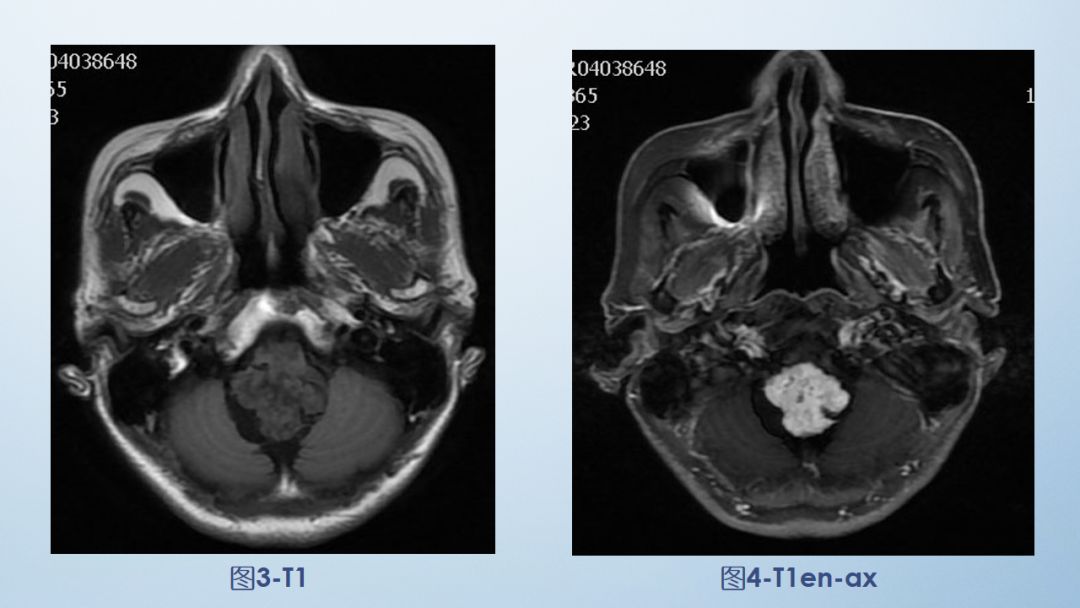

FLAIR图及T1矢状位增强:白色箭头所示小脑延髓池内可见实性占位病变,形态不规则,呈分叶状,病变边界清晰,边缘见血管流空信号影如蓝色箭头所示。

影像描述:小脑延髓池内见不规则异常信号影,呈等及稍长T1长T2信号,内部信号不均,边缘见稍粗大流空信号血管影,FLAIR病灶中心少许片状低信号,增强呈明显强化,DWI不均低信号,ADC不均高信号。小脑半球、延髓、第四脑室受压变形。临近延髓受压变窄,呈长T1长T2信号。

影像诊断:后颅窝实性占位病变,考虑实性血管母细胞瘤。